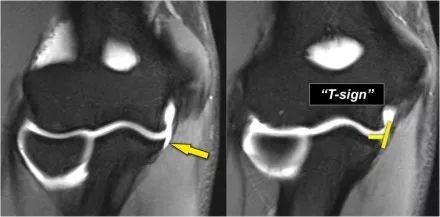

下面是一名18岁的棒球投手,内侧肘部疼痛。看到局部撕裂产生'T标志'。

下面的图像,请注意,前束是完整的,并牢固地附着在崇高的结节上(黄色箭头)。在接下来的两张图像上,有一些软组织水肿,后面有更多异常信号(红色箭头)。所以我们怀疑后束的病理学。现在你记得轴向图像可能会有所帮助。